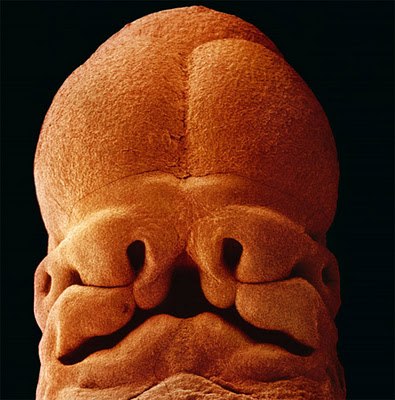

Эволюция эмбриона на фотографиях Леннарта Нильсона — шведского фотографа и ученого, пионера медицинской фотографии. Он потратил 10 лет жизни, чтобы снять на пленку эволюцию эмбриона от зачатия до рождения. Уникальные кадры с места, откуда люди делают перв10 写真